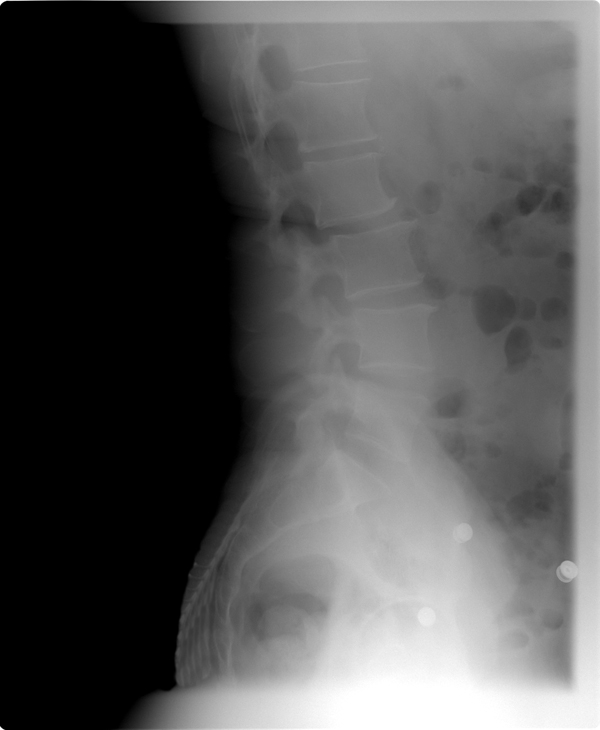

Xrays revealed my spine is bent a bit to the left, which reconciles with my muscle spasms. When they occur my right leg becomes about 1 – 2 inches shorter. I asked if chicken or egg – whether spine driven or muscle driven, the doctor thinks spine driven and correctable. Best guess is 6 to 9 treatments including pressure point massage. So, I’m going down this path. New for me. Science or art?